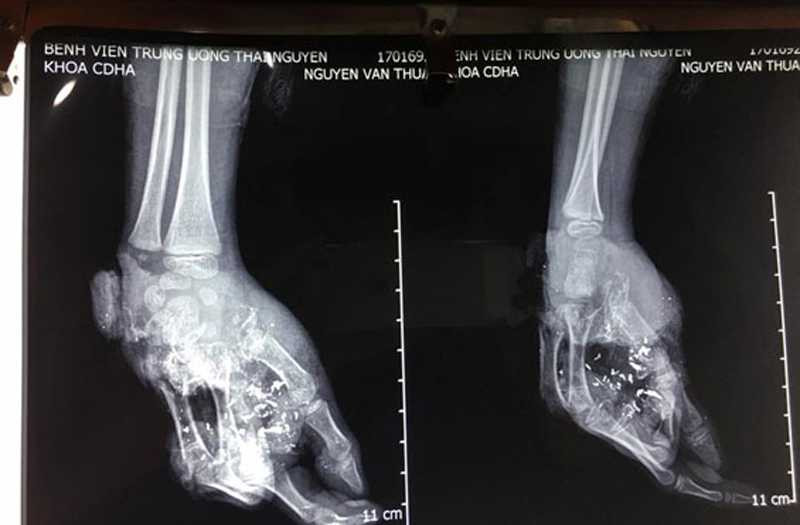

Hình ảnh bàn tay phải bị dập nát

Trao đổi với chúng tôi, bác sĩ Nguyễn Thanh Tùng cho biết, quả pin phát nổ đã gây tổn thương nghiêm trọng. Bàn tay phải của Thuận mất toàn bộ xương bàn ngón giữa, áp út và ngón út; mất toàn bộ bờ ngoài bàn tay; tổn thương toàn bộ hệ thống gân bàn tay, xương bàn tay và gân cơ.

Ngoài ra, khu vực lòng bàn tay có nhiều dị vật mảnh vỡ bằng kim loại. Dự kiến, cháu Thuận sẽ tiếp tục được phẫu thuật ít nhất 1 lần nữa để chuyển vạt và ghép da vào những vết thương hở.